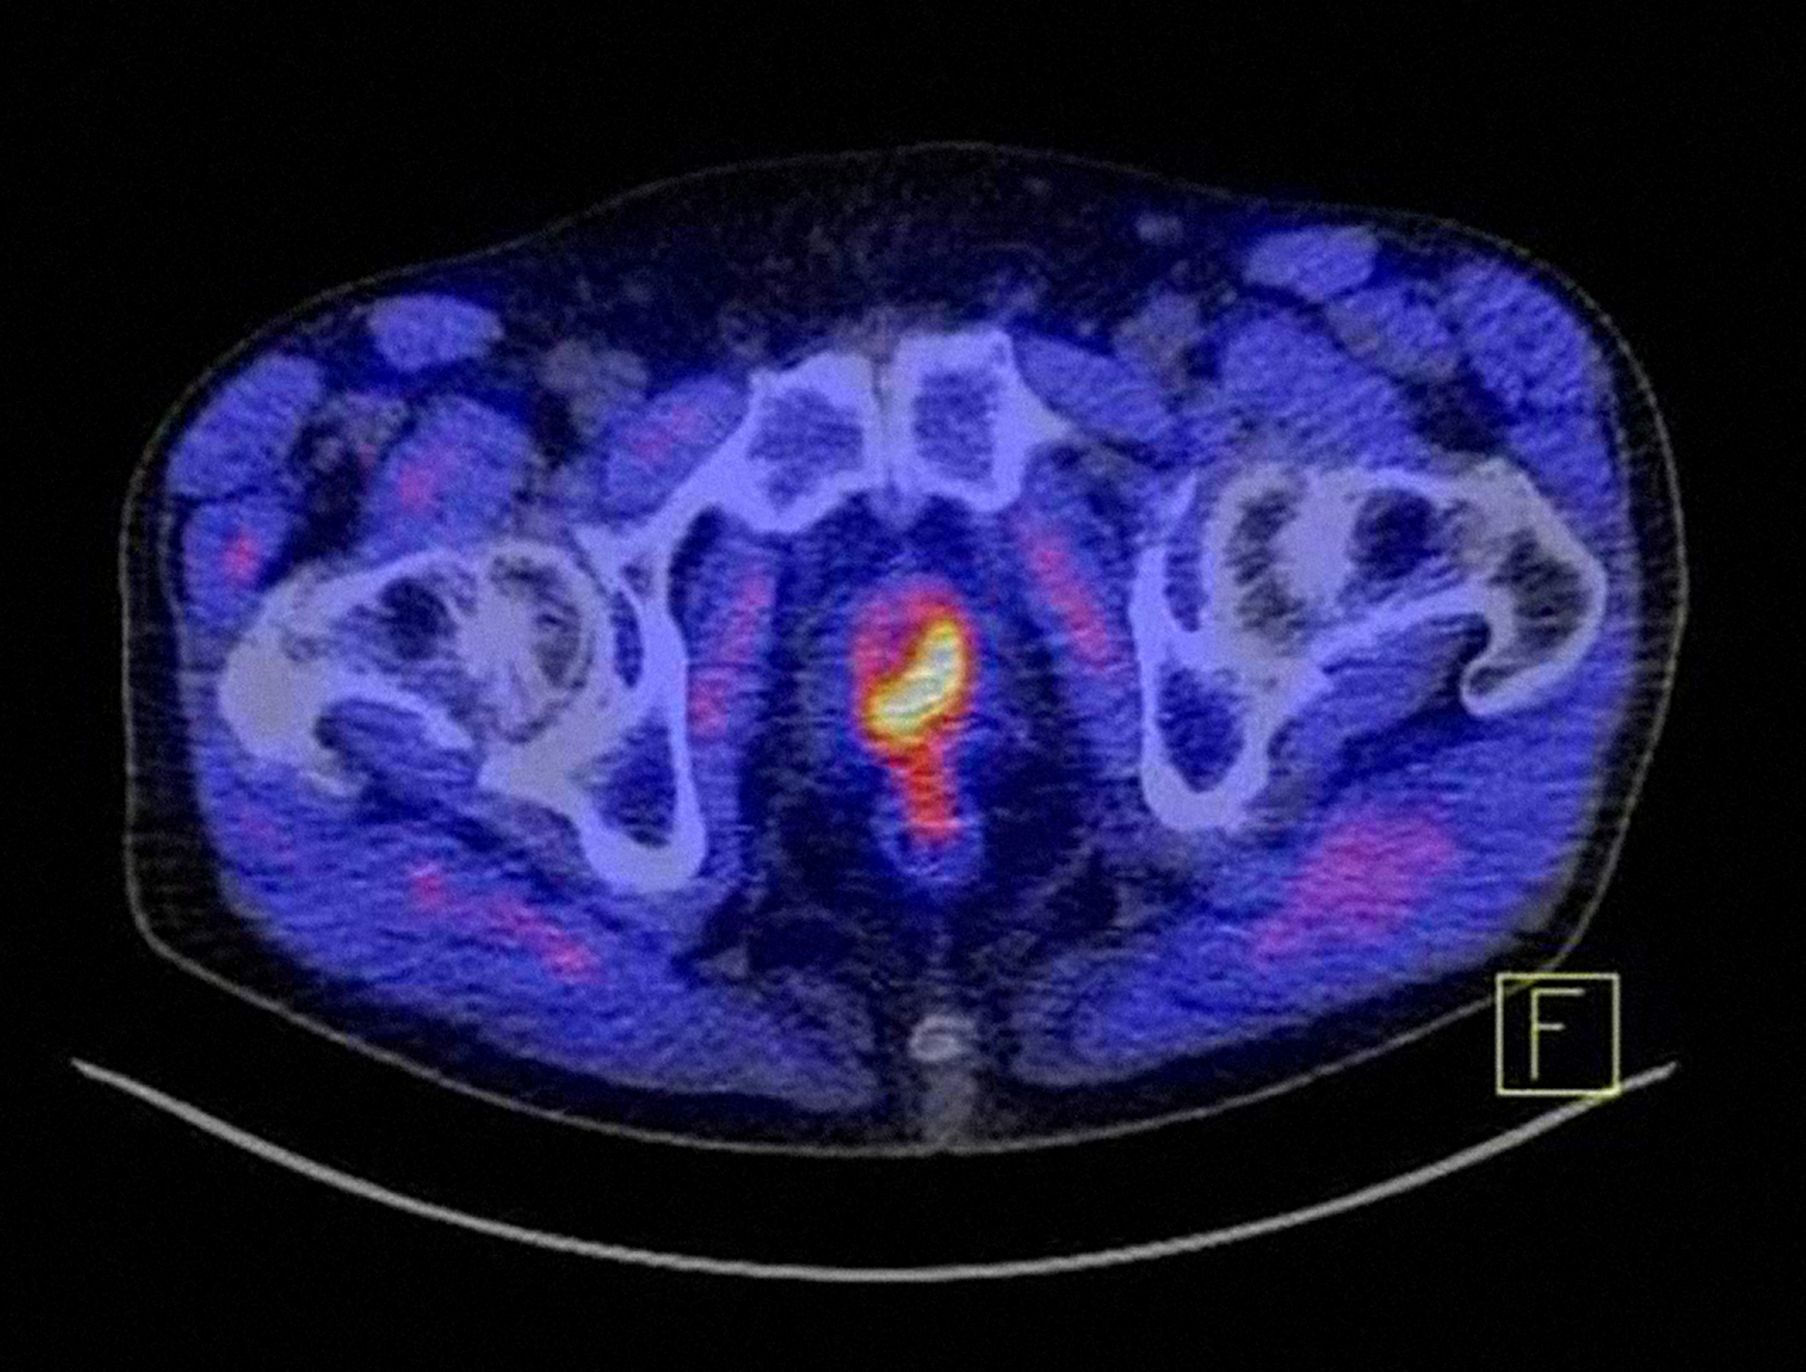

Im CT wird ein Prostatakarzinom markant dargestellt.

Der 8. Patienteninformationstag des Prostatakarzinomzentrums des Uniklinikums Würzburg am 18. April 2026 beschäftigt sich mit Vorsorge, Diagnostik und Therapie. Das Bild zeigt, wie markant ein Prostatakarzinom unter Zuhilfenahme des Tracers PSMA im PET-CT als gelb-rotes Objekt dargestellt wird. © UKW